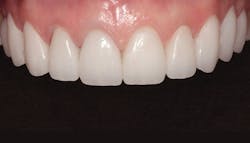

The final result can be seen from the occlusal view in Figure 9 and the retracted facial view in Figure 10. The patient’s new smile can be seen in Figure 11. Utilizing IPS e.max crowns and veneers, we were able to enhance the patient’s smile by creating a lighter color and a wider, more attractive look.

Figure 10: Retracted facial view of the final restoration

Figure 11: The patient’s new smile